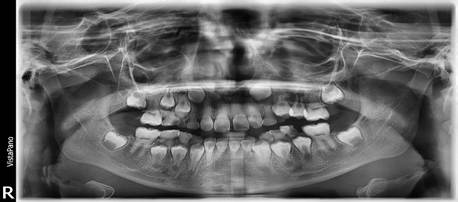

Figura 9. Análisis radiográfico

Al análisis radiográfico observamos un paciente en dentición mixta. Las piezas deciduas en su proceso fisiológico normal de reabsorción radicular.

Figura 10. Radiografías periapicales

Se observa a mayor detalle la obliteración de los conductos radiculares en las piezas permanentes, hallazgo radiográfico común en pacientes con amelogénesis imperfecta.